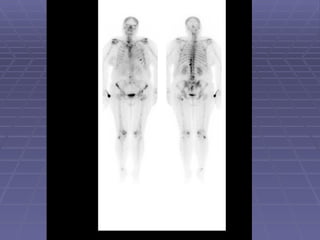

Metastatic Bone Disease and Image Findings The hallmark of metastatic bone disease is multiple foci of increased osteoblastic activity in bony skeleton. However, single lesion could be also metastatic.

Metastatic Bone Diseaseand Image Findings The hallmark of metastatic bone disease is multiple foci of increased osteoblastic activity in bony skeleton. However, single lesion could be also metastatic.

Metastatic Bone DiseaseBone scan is an extremely important tool in decision making during management of cancer patients. Any cancer potentially could cause bone metastatic disease. However, prostate, breast and lung cancers have propensity to metastasize to bone.

Metastatic Bone Diseaseand Bone Pain About 80% of patients with known cancer and bone pain have metastases documented by bone scan. 30 – 50% of patients with metastatic bone disease do not have bone pain.